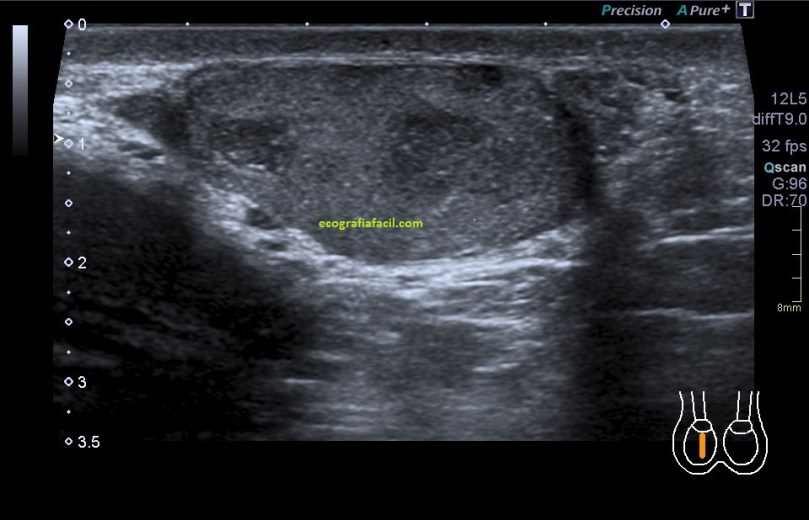

En la imagen 5 podemos ver afectación testícular de las mismas características ecográficas, pero existen varios focos de lesión. imágenes 4 y 5 son pacientes distintos.

El aspecto de esta lesión, su semiología ya la has visto en estos dos casos diferentes, pero tienen en común, de modo general, hipoecogenicidad, heterogenicidad, bordes irregulares, con aspecto polilobulado y de tamaño y número variable.